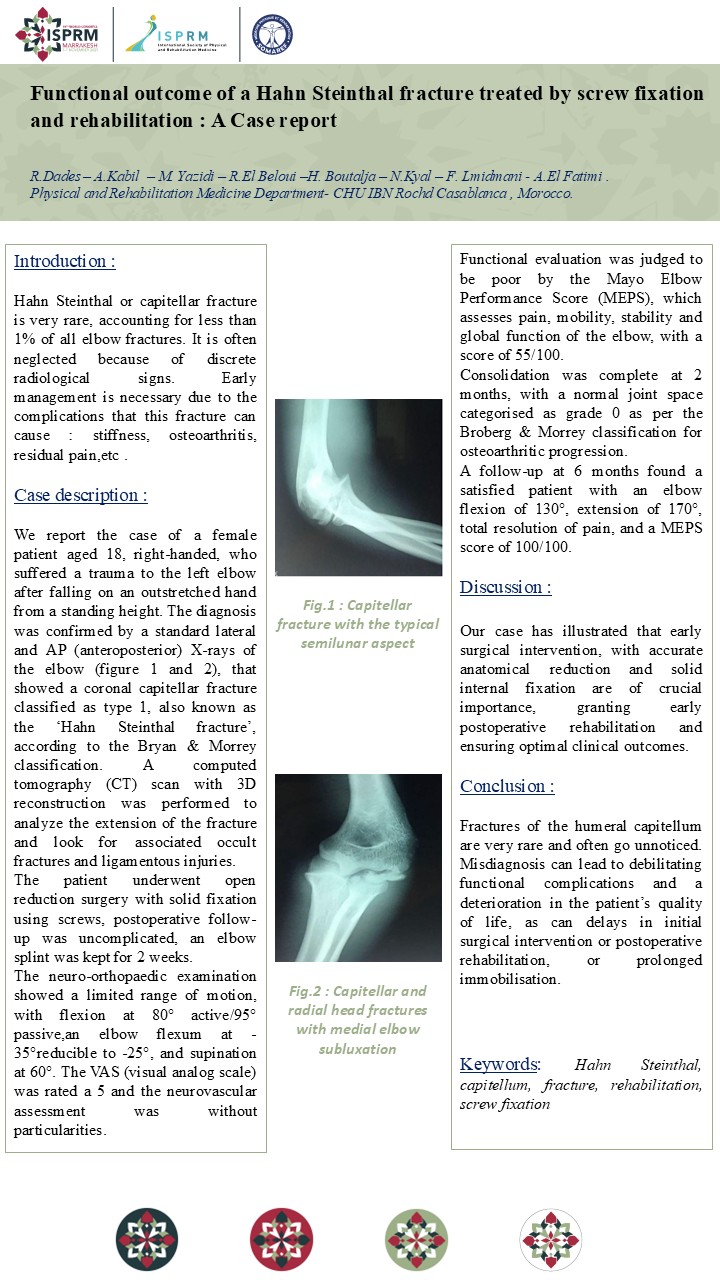

Musculoskeletal

Functional outcome of a Hahn Steinthal fracture treated by screw fixation and rehabilitation : a case report